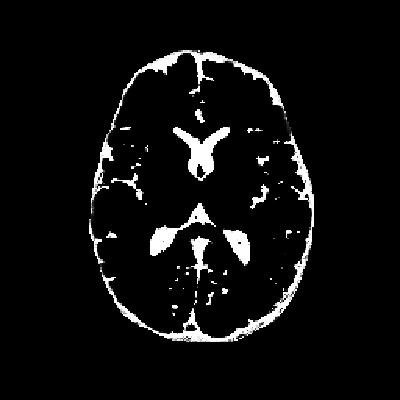

- 原始图像:如图1所示,原始图像中存在较多噪声,直接使用FCM算法进行分割会导致结果不准确。